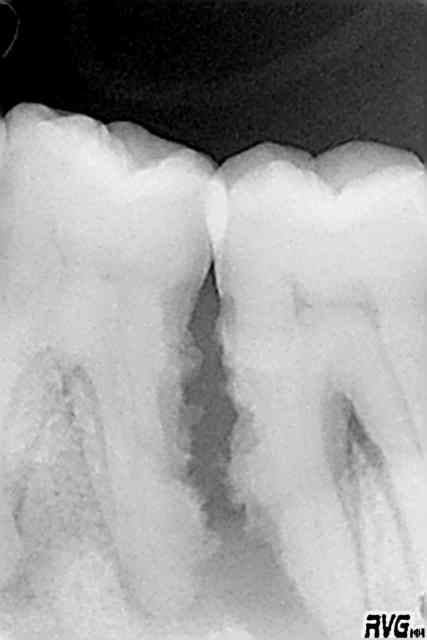

Juste un autre cas pour vous démontrer que je n'ai aucune action chez Straumann et Emdogain.

Paro aggressive généralisée. Patiente en traitement initial causal. Instruction + depuration/rotscaling.

Radio initiale de 43 :

Radio de cicatrisation lors de l'évaluation à + 6 mois.

Aucune chirurgie régénerative. Juste depuration/rotscaling et maintenance !! :